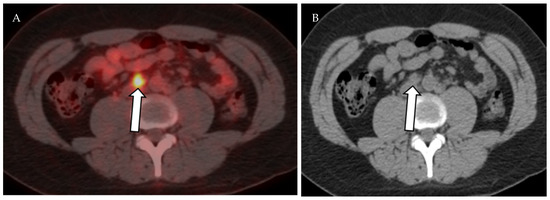

Lymphoscintigraphy